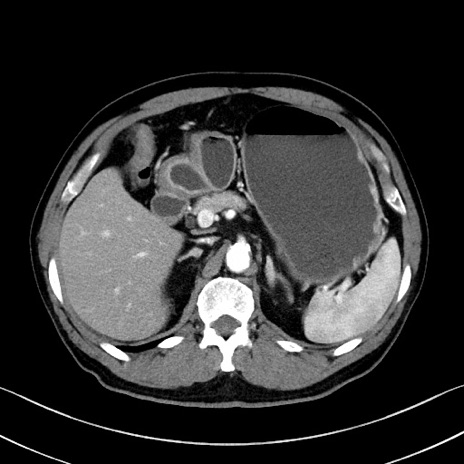

症例35(横断像)

【症例】70歳代 男性

【主訴】腹部膨満、嘔吐

【現病歴】昨日より腹部膨満感出現。本日増悪し、仙痛出現。嘔吐あり、受診。

【既往歴】糖尿病、胆摘後

【身体所見】BP 149/80mmHg、HR 74/min、BT 35.9℃、腹部:膨満、軟、圧痛なし。腸雑音減弱あり。上腹部正中切開瘢痕あり。

【データ】WBC 13500、CRP 1.72